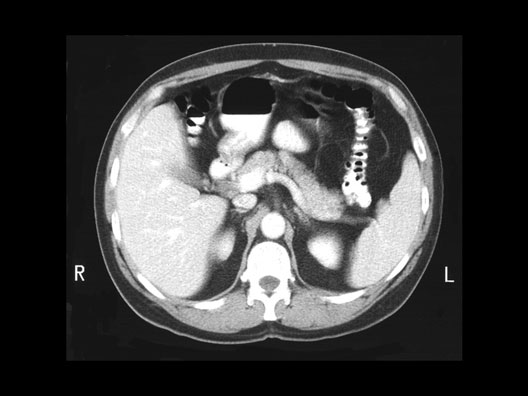

Splenic Vein

Roll mouse over image to display labels.

1. Portal vein

2. Colon

3. Stomach

4. Pancreas

5. Splenic vein

6. Spleen

7. Left Adrenal gland

8. Left Kidney

9. Aorta

10. Inferior Vena Cava

11. Right Kidney

12. Right Adrenal Gland

13. Liver